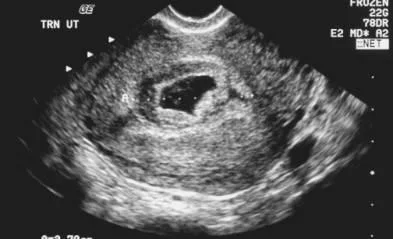

Threatened miscarriage

Clinical feature:

- Amenorrhea.

- Mild bleeding (spotting).

- Mild pain.

On examination:

- Uterus corresponding to the date.

- PV: closed cervical os.

Investigations:

- Pregnancy test (hCG): +ve.

- US: viable intra uterine fetus.

Management:

- reassurance.

- Rest.

- Repeated U/S

- Progesterone support.

~ COMMON & MOSTLY DOES NOT RESULT in a MISCARRIAGE

BLEEDING from CLOSED CERVIX